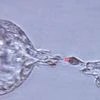

India's first babies to be born without a hereditary cancer-causing gene

How can one prevent against cancer? By removing the trouble-making gene before it enters the world